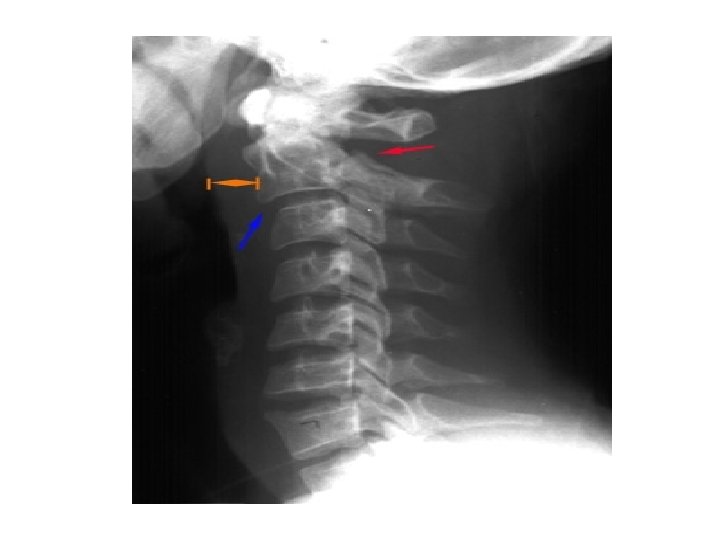

• Check : • B - individual vertebrae • C - cartilage • D - disc • S - soft tissue • <7 mm at C 3 • <21 mm at C 7 • no more than vertebral body width at C 7 • Predental space – • 5 mm child • 3 mm adult • Fanning of spinous processes

ANTERIOR SUBLUXATION • Disruption of the posterior ligament complex. Anterior subluxation of C 4 on C 5 is characterized by widening of the interspinous space (arrowhead), subluxation of the C 4 -C 5 interfacetal joints (arrows), and anterior rotation of the C 4 vertebra relative to C 5.

• • • Stable but potentially unstable during flexion Mechanism : hyperflexion Disruption of posterior ligament complex, anterior intact • • Stable – loss of normal cervical lordosis anterior displacement of body fanning of interspinous distance • • • Unstable – anterior subluxation >4 mm assoc. compression fracture >25% of affected body increase or decrease in normal disc space fanning of interspinous distance • •